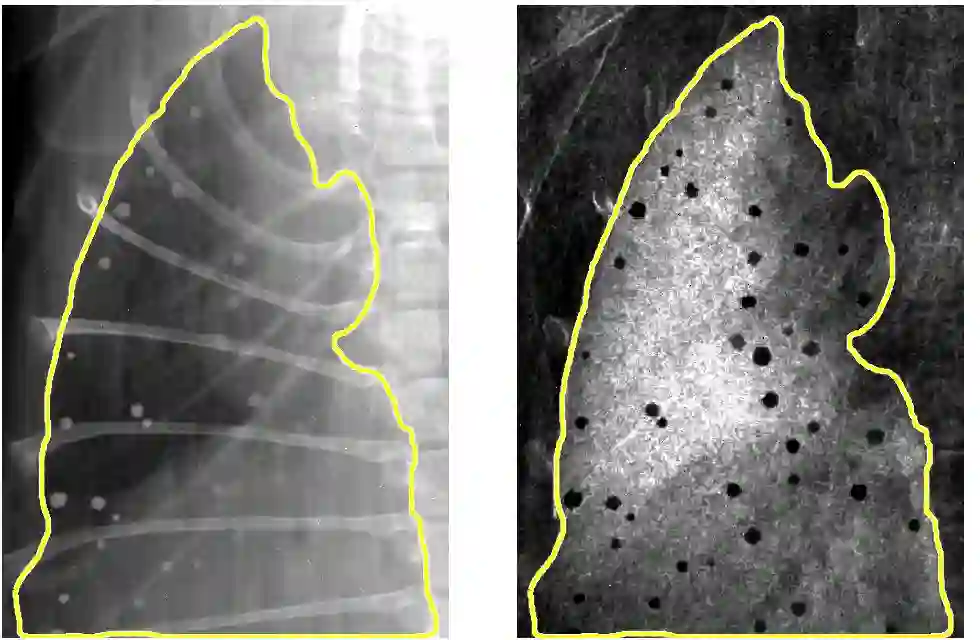

Low-dose computed tomography (LDCT) is the current standard for lung cancer screening, yet its adoption and accessibility remain limited. Many regions lack LDCT infrastructure, and even among those screened, early-stage cancer detection often yield false positives, as shown in the National Lung Screening Trial (NLST) with a sensitivity of 93.8 percent and a false-positive rate of 26.6 percent. We aim to investigate whether X-ray dark-field imaging (DFI) radiograph, a technique sensitive to small-angle scatter from alveolar microstructure and less susceptible to organ shadowing, can significantly improve early-stage lung tumor detection when coupled with deep-learning segmentation. Using paired attenuation (ATTN) and DFI radiograph images of euthanized mouse lungs, we generated realistic synthetic tumors with irregular boundaries and intensity profiles consistent with physical lung contrast. A U-Net segmentation network was trained on small patches using either ATTN, DFI, or a combination of ATTN and DFI channels.Results show that the DFI-only model achieved a true-positive detection rate of 83.7 percent, compared with 51 percent for ATTN-only, while maintaining comparable specificity (90.5 versus 92.9 percent). The combined ATTN and DFI input achieved 79.6 percent sensitivity and 97.6 percent specificity. In conclusion, DFI substantially improves early-tumor detectability in comparison to standard attenuation radiography and shows potential as an accessible, low-cost, low-dose alternative for pre-clinical or limited-resource screening where LDCT is unavailable.